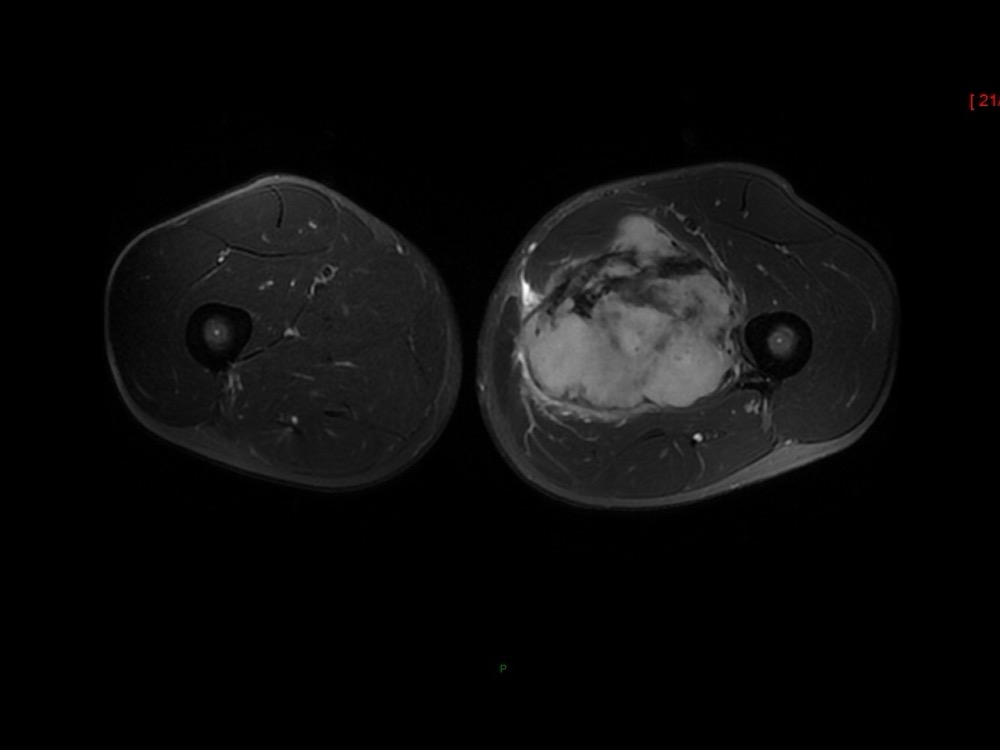

Moalla / Mihoubi-Bouvier / Drapé 18/05/2022